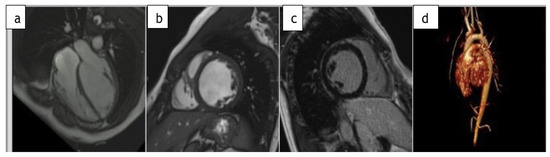

2. Case Report